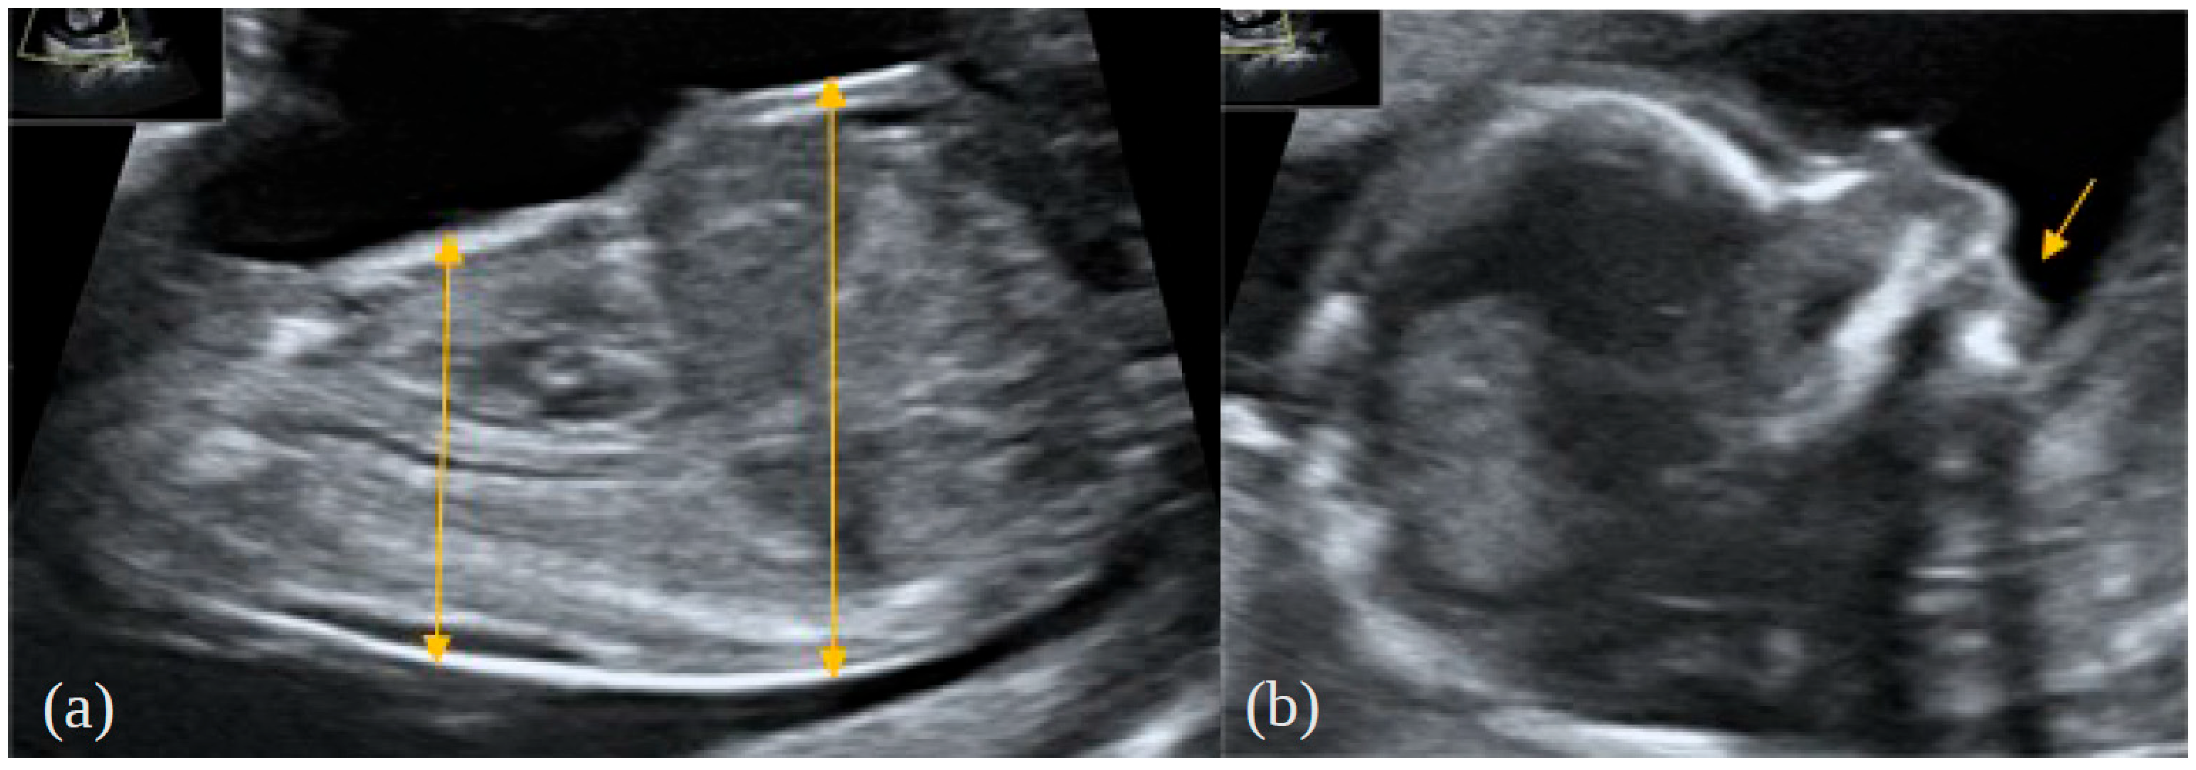

2. Case Report